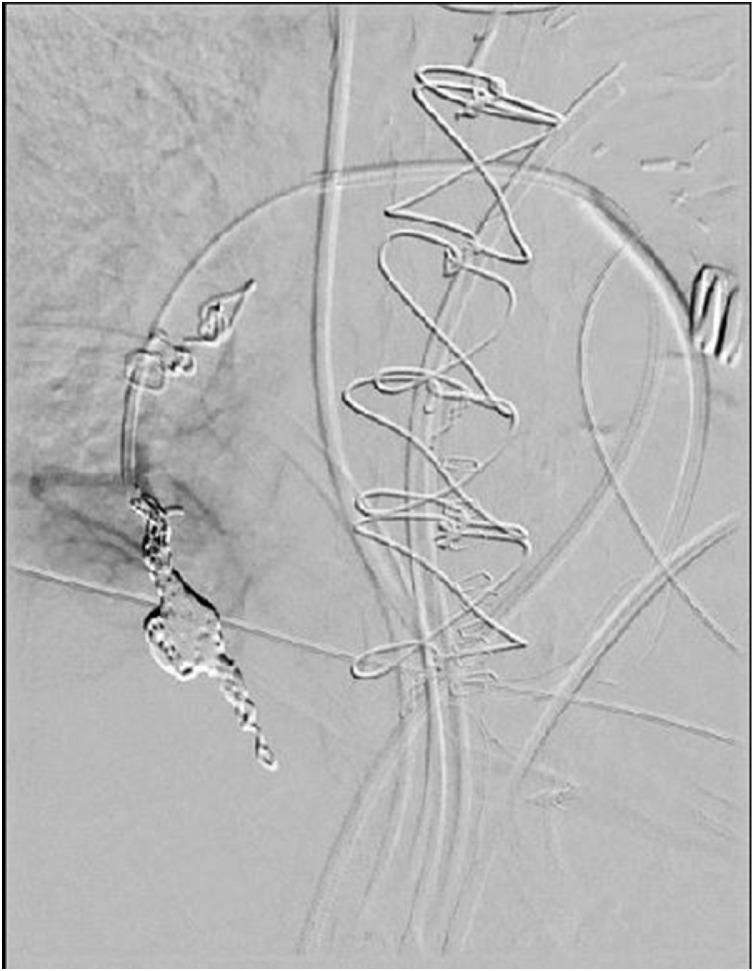

Successful percutaneous embolization of an intraoperative swan ganz catheter-related pulmonary artery injury.

Intraoperative pulmonary artery injury due to Swan Ganz catheterization is a rare but potentially life-threatening injury which demands rapid recognition and treatment. Subsequent pseudoaneurysm formation can occur if not immediately recognized, and percutaneous embolization is a viable option for treatment in most settings. We report a case of a 59-year-old female who underwent coronary artery bypass surgery and suffered an intraoperative Swan Ganz catheter-related injury which led to life threatening hemorrhage with subsequent pulmonary artery pseudoaneurysm formation that was successfully embolized. This case report is pathognomonic for this injury and discusses risk factors, presentation, and treatment options of this rare but serious injury.